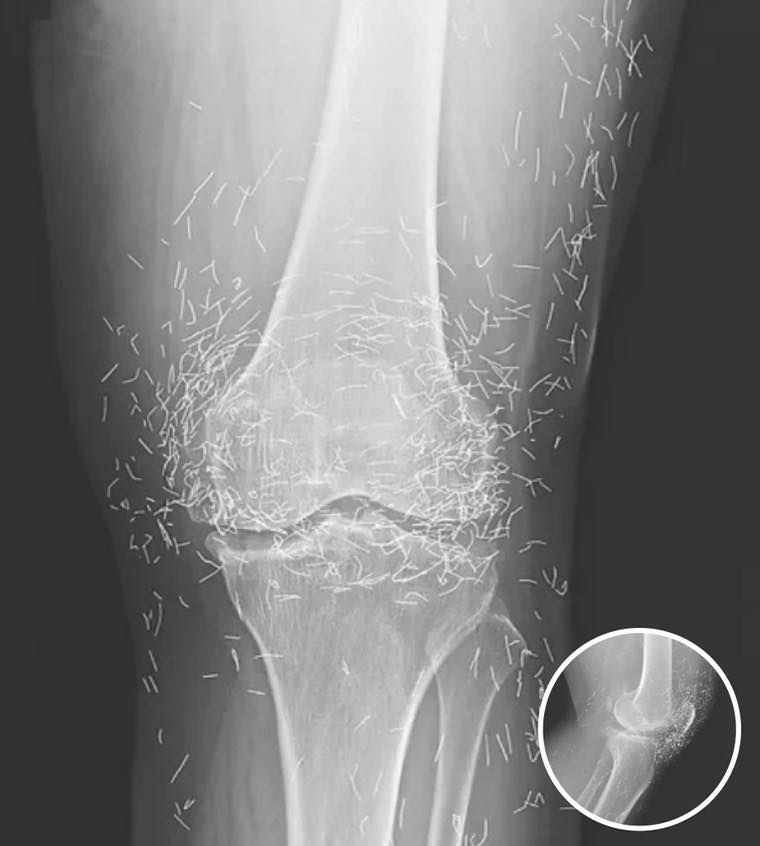

On February 21, 2026, a routine medical examination led to an unexpected discovery that has sparked significant discussions around the safety of alternative therapies, specifically acupuncture. A 65-year-old woman from South Korea, who has been struggling with severe joint pain due to osteoarthritis, was subjected to an X-ray that unveiled hundreds of tiny gold needles embedded in her knee tissue. This revelation raises profound questions about the practices we turn to when conventional treatments fail and highlights the complexities of navigating alternative medicine.

Acupuncture is a traditional Chinese medicine practice that involves inserting thin needles into specific points on the body to alleviate pain and treat various ailments. It has gained popularity worldwide, particularly in Asian countries like South Korea, where it is often utilized for managing arthritis symptoms. In the case of this South Korean woman, she turned to acupuncture after traditional treatments failed her. However, her treatment plan included the controversial practice of leaving gold needles in place, designed to offer continuous stimulation to the affected area. The practice of acupuncture itself is steeped in history, with roots that trace back over 2,500 years. Traditionally, it is based on the belief that energy (or “qi”) flows through pathways in the body, and by inserting needles at specific points, practitioners can restore balance and promote healing. While many patients report positive outcomes, these experiences are often anecdotal and not universally replicable. The lack of standardized practices and rigorous scientific study can lead to widely varying results, raising concerns about patient safety and the efficacy of treatments like those used in this case.

While the intention behind using gold needles may have been to provide long-term relief, medical professionals warn of the potential dangers associated with leaving foreign objects within the body. Dr. Ali Guermazi, a radiology professor at Boston University, emphasizes that the human body is not equipped to handle foreign materials. According to Dr. Guermazi, this can lead to a series of complications, including inflammation, infection, and the formation of abscesses. He states, “The human body doesn’t like foreign material. It reacts with defense mechanisms — starting with inflammation and forming fibrous tissue around the object.” This cautionary perspective is echoed across medical literature, where numerous case studies highlight instances of patients experiencing adverse effects from retained needles. For example, patients have reported chronic pain, persistent swelling, and in severe cases, the need for surgical intervention to remove the embedded objects. The implications of such cases underscore the importance of informed consent, urging patients to be fully aware of potential risks associated with alternative therapies.

In addition to the immediate health risks, the presence of retained needles poses significant complications for medical diagnostics. Retained foreign bodies can obscure anatomical details on X-rays, complicating the interpretation of imaging results. Moreover, patients with metallic objects in their bodies face serious restrictions when it comes to medical procedures like MRI scans. The magnetic force during an MRI can cause these needles to move, potentially leading to severe damage, including puncturing blood vessels, which could result in life-threatening situations. Furthermore, the diagnostic ambiguity introduced by foreign materials can lead to misdiagnoses. Medical practitioners may overlook critical signs of existing conditions while attributing symptoms to retained needles, thereby delaying appropriate treatment. This scenario highlights the need for clear communication between alternative therapy providers and conventional medical practitioners, ensuring that all parties involved are aware of a patient’s complete medical history and any alternative treatments undertaken.

The case of the 65-year-old South Korean woman serves as a cautionary tale in the realm of alternative therapies. While she sought relief from debilitating joint pain, her X-rays serve as a stark reminder of the potential risks associated with extreme alternative medicine practices. Health practitioners and patients alike must approach treatments — especially those involving the insertion of foreign materials into the body — with caution and thorough understanding. It is crucial to weigh the benefits against the potential risks, ensuring that the pursuit of relief does not come at the cost of additional health complications. As this case illustrates, the allure of immediate relief can cloud judgment, leading individuals to make choices that could have long-term consequences. It is crucial for practitioners to engage in thorough discussions with their patients about available options, including the risks and benefits of each treatment approach. This dialogue fosters informed decision-making, enabling patients to choose therapies that align with their health goals while minimizing potential hazards.